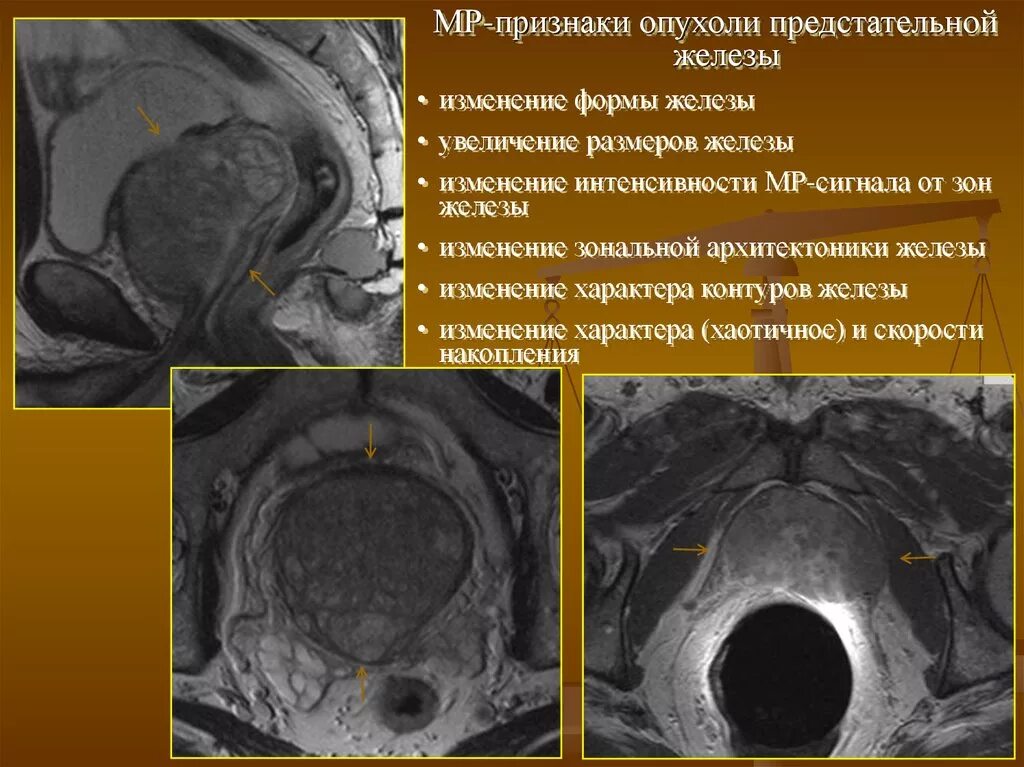

УВТ предстательной железы. Кальцинат предстательной железы. Cancer предстательной железы Предстательная железа MRT. Мультипараметрическое мрт предстательной железы. Предстательная железа кт норма. Аденома предстательной железы мрт

Предстательная железа MRT. Мультипараметрическое мрт предстательной железы. Предстательная железа кт норма. Аденома предстательной железы мрт Гистосканнинг предстательной железы. Трансректальная биопсия предстательной железы под контролем УЗИ. Ангиография предстательной железы. Лимфоузлы в предстательной железе

Объемное образование в предстательной железе кт. Местно распространенный

Объемное образование в предстательной железе кт. Местно распространенный Злокачественное Перерождение предстательной железы

Злокачественные новообразования простаты. Злокачественная опухоль предстательной железы в пожилом возрасте. Новообразования простаты злокачественной природы Сосудисто нервный пучок предстательной железы. Экстракапсулярная экстензия предстательной железы что это. Лучевая диагностика предстательной железы. Инвазия капсулы предстательной железы

Сосудисто нервный пучок предстательной железы. Экстракапсулярная экстензия предстательной железы что это. Лучевая диагностика предстательной железы. Инвазия капсулы предстательной железы Предстательная железа у мужчин. Представительна яжелеза. Опухальпредседательнойжелезы